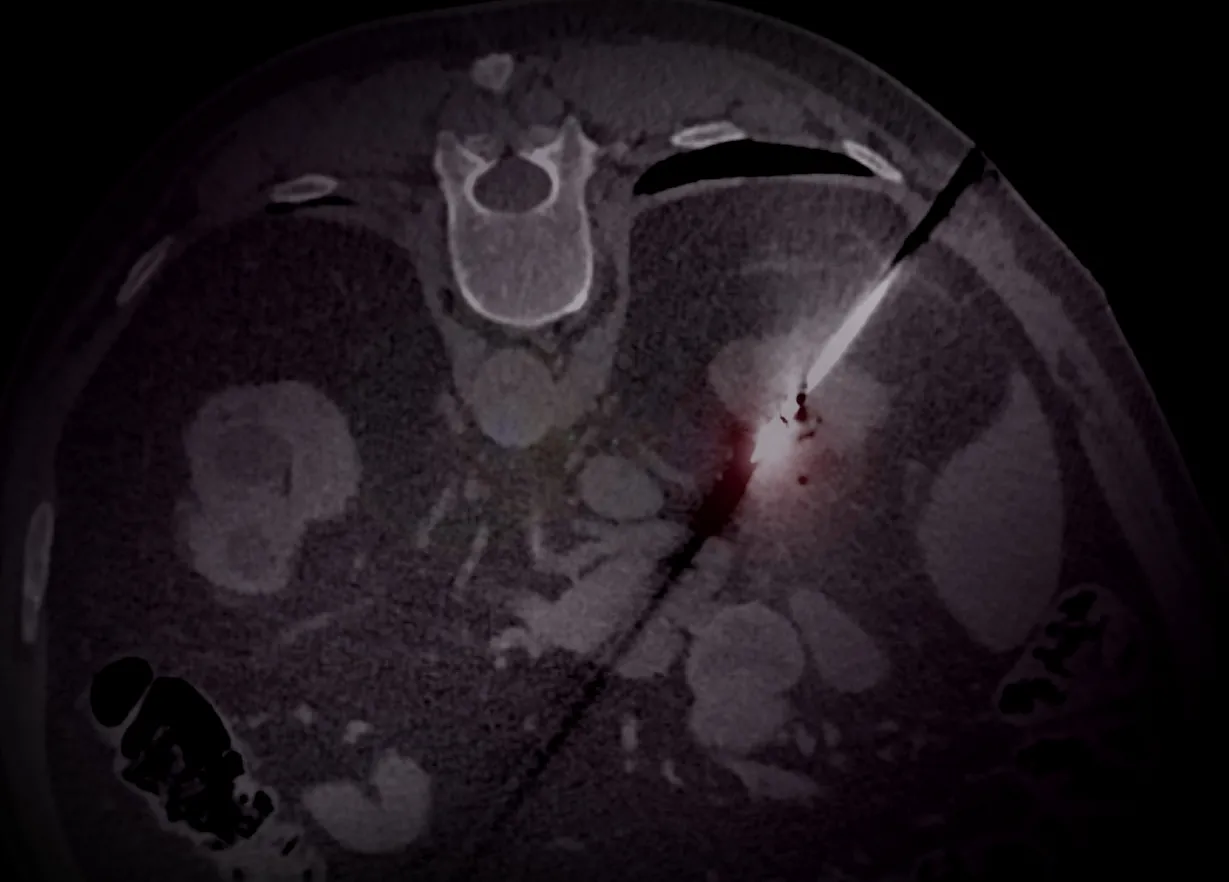

NEW MODULE RELEASE! Interventional Radiology - General

Discover the world of interventional radiology! This module provides an overview of the basic principles and is the perfect starting point to see exactly what the field entails.

Interventional Radiology - General

NEW MODULE RELEASE! Interventional Radiology - Non-Oncological

Dive into our new module and learn everything there is to know about the non-oncological procedures. Check it out now and elevate your expertise!

Interventional Radiology - Non-Oncological